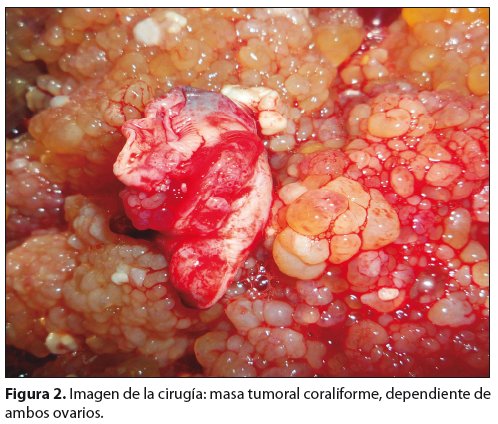

Se realiza laparotomía diagnóstica, etapificadora y citoreductora: histerectomía abdominal total, ooforectomía bilateral, (fig. 2) omentectomía, apendicectomía, biopsia de correderas parietocólicas derecha e izquierda, cepillado de cúpula diafragmática, citología de líquido ascítico.

El cistoadenocarcinoma seroso, (25%) es de gran tamaño con proliferación infiltrativa que perfora la cápsula con diseminación peritoneal. Está constituido por estructuras papilares friables con micro calcificaciones concéntricas llamadas cuerpos de Psammoma6. Histológicamente el blastoma está representado por una proliferación epitelial con características de atipia y que forma estructuras papilares de distinto grado de diferenciación con ejes conectivos delgados4.